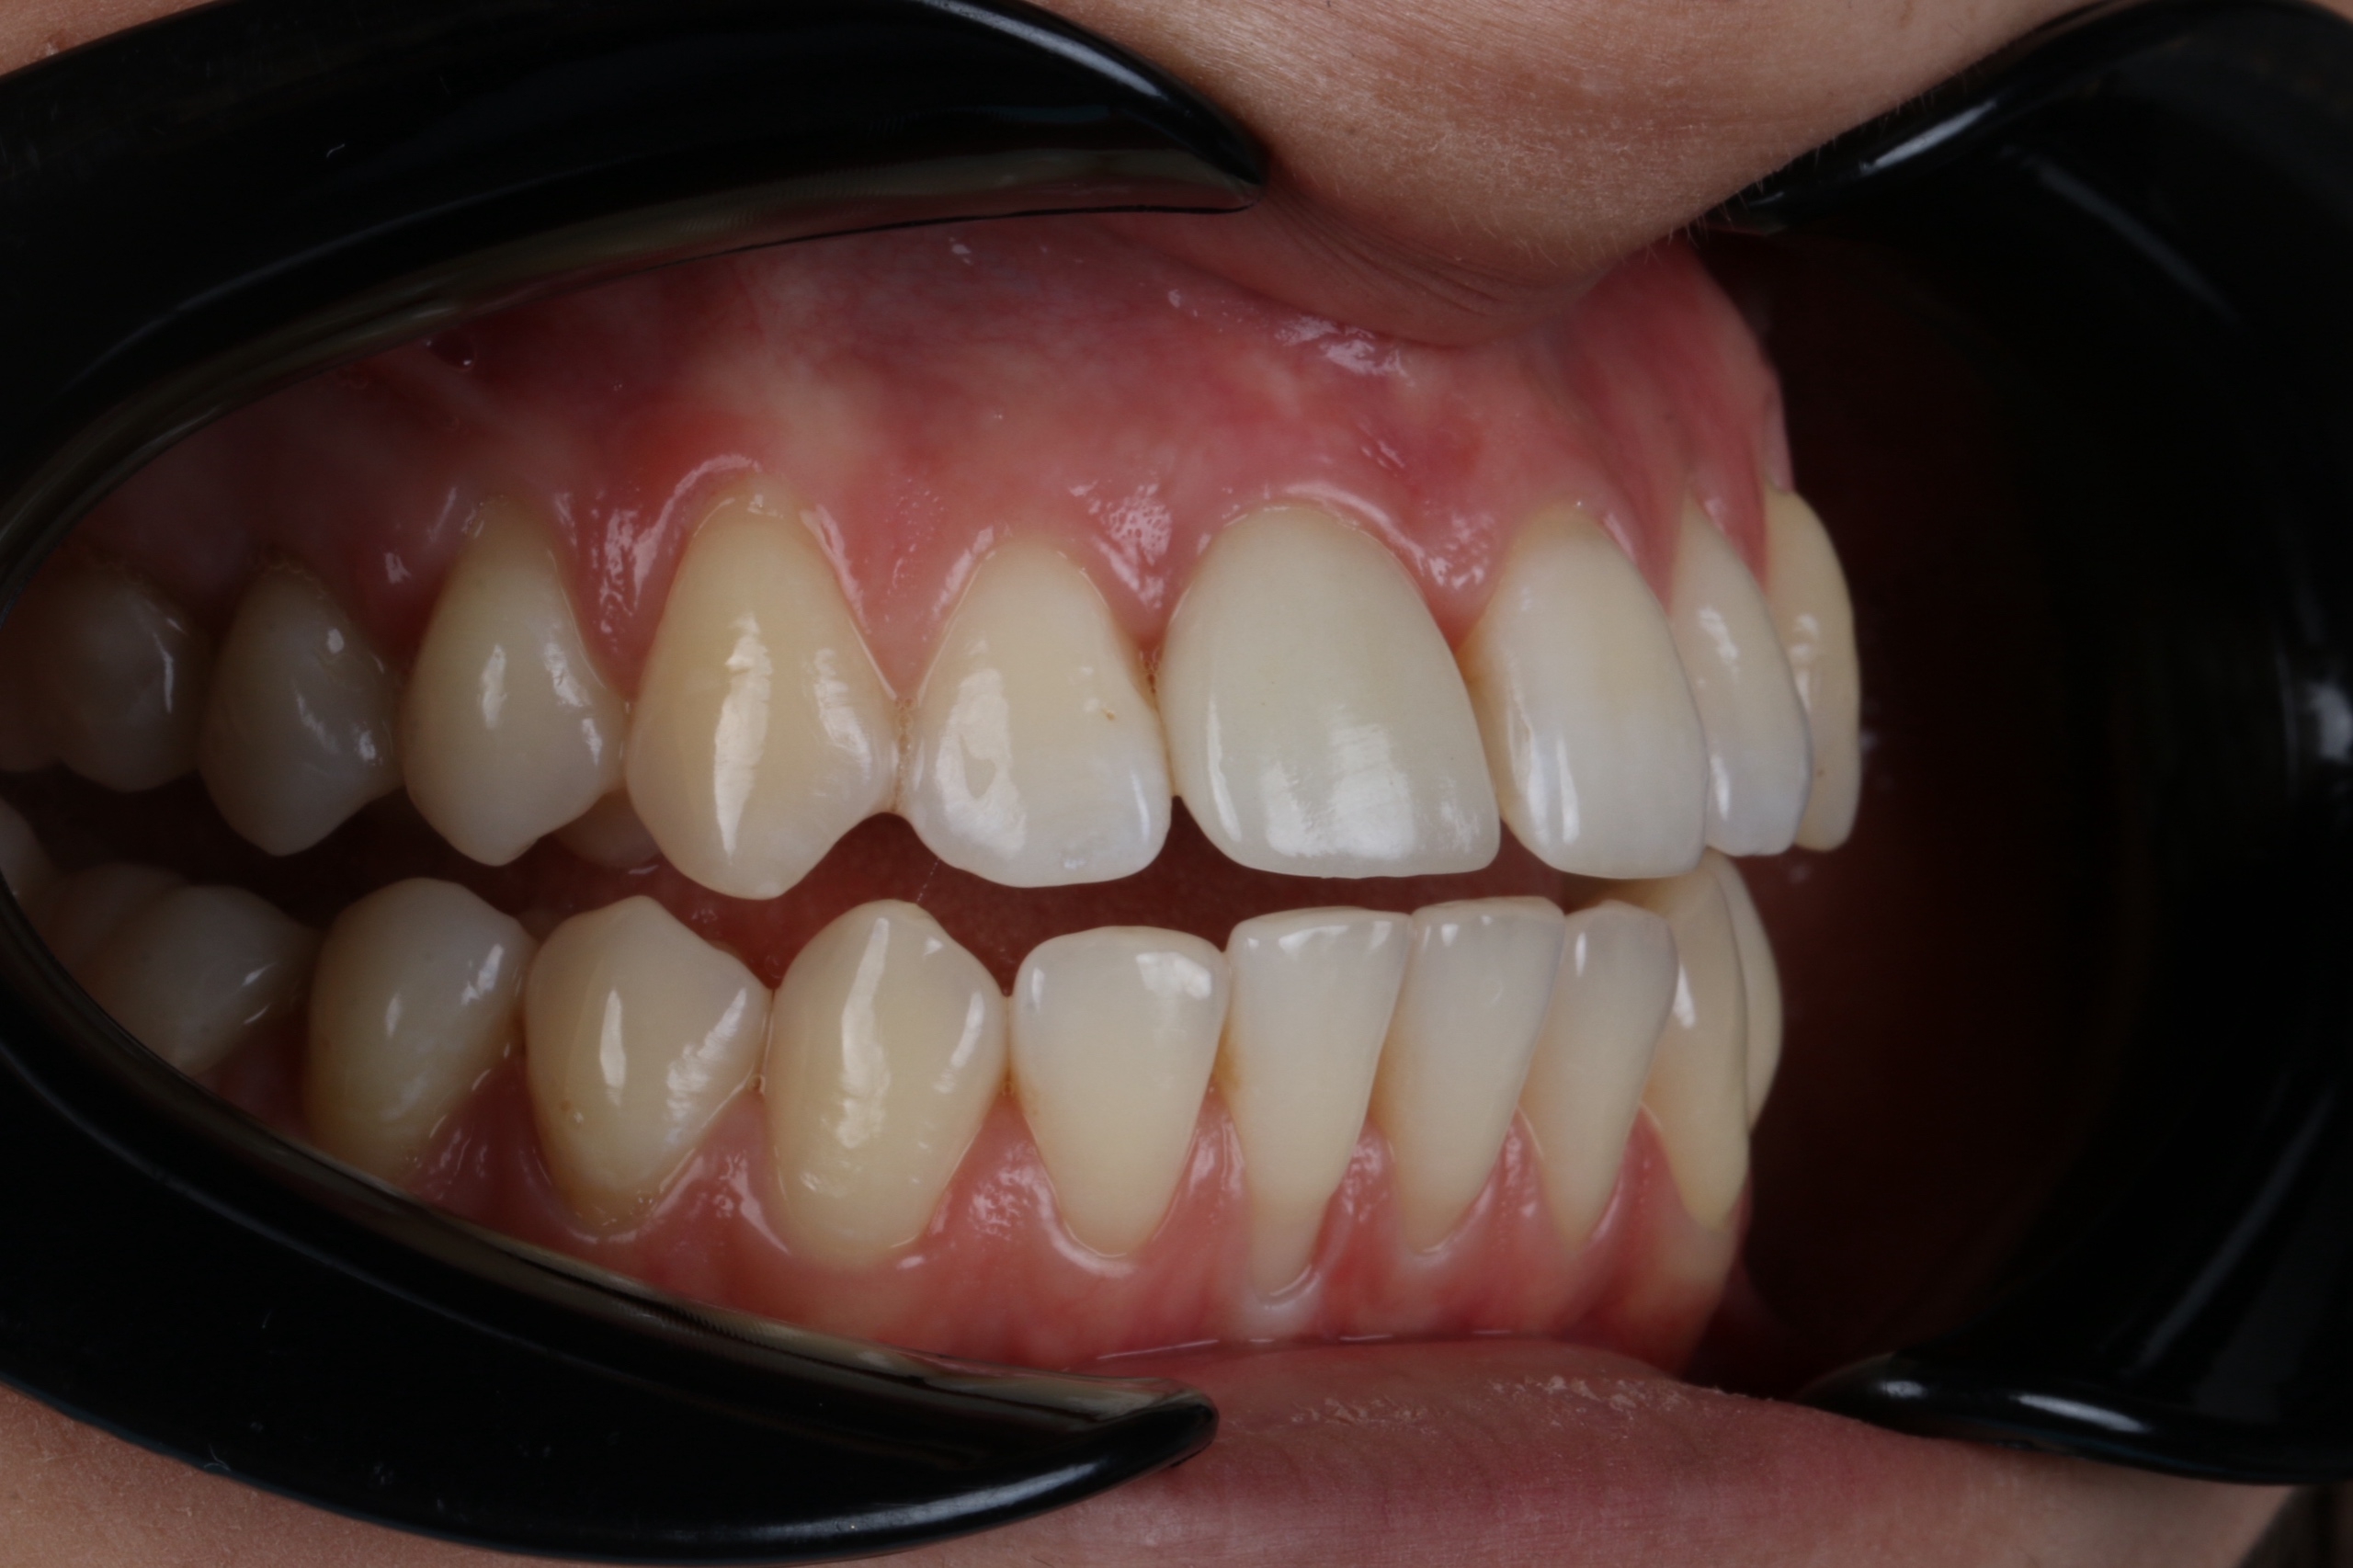

Когда устанавливать имплант после удаления зуба